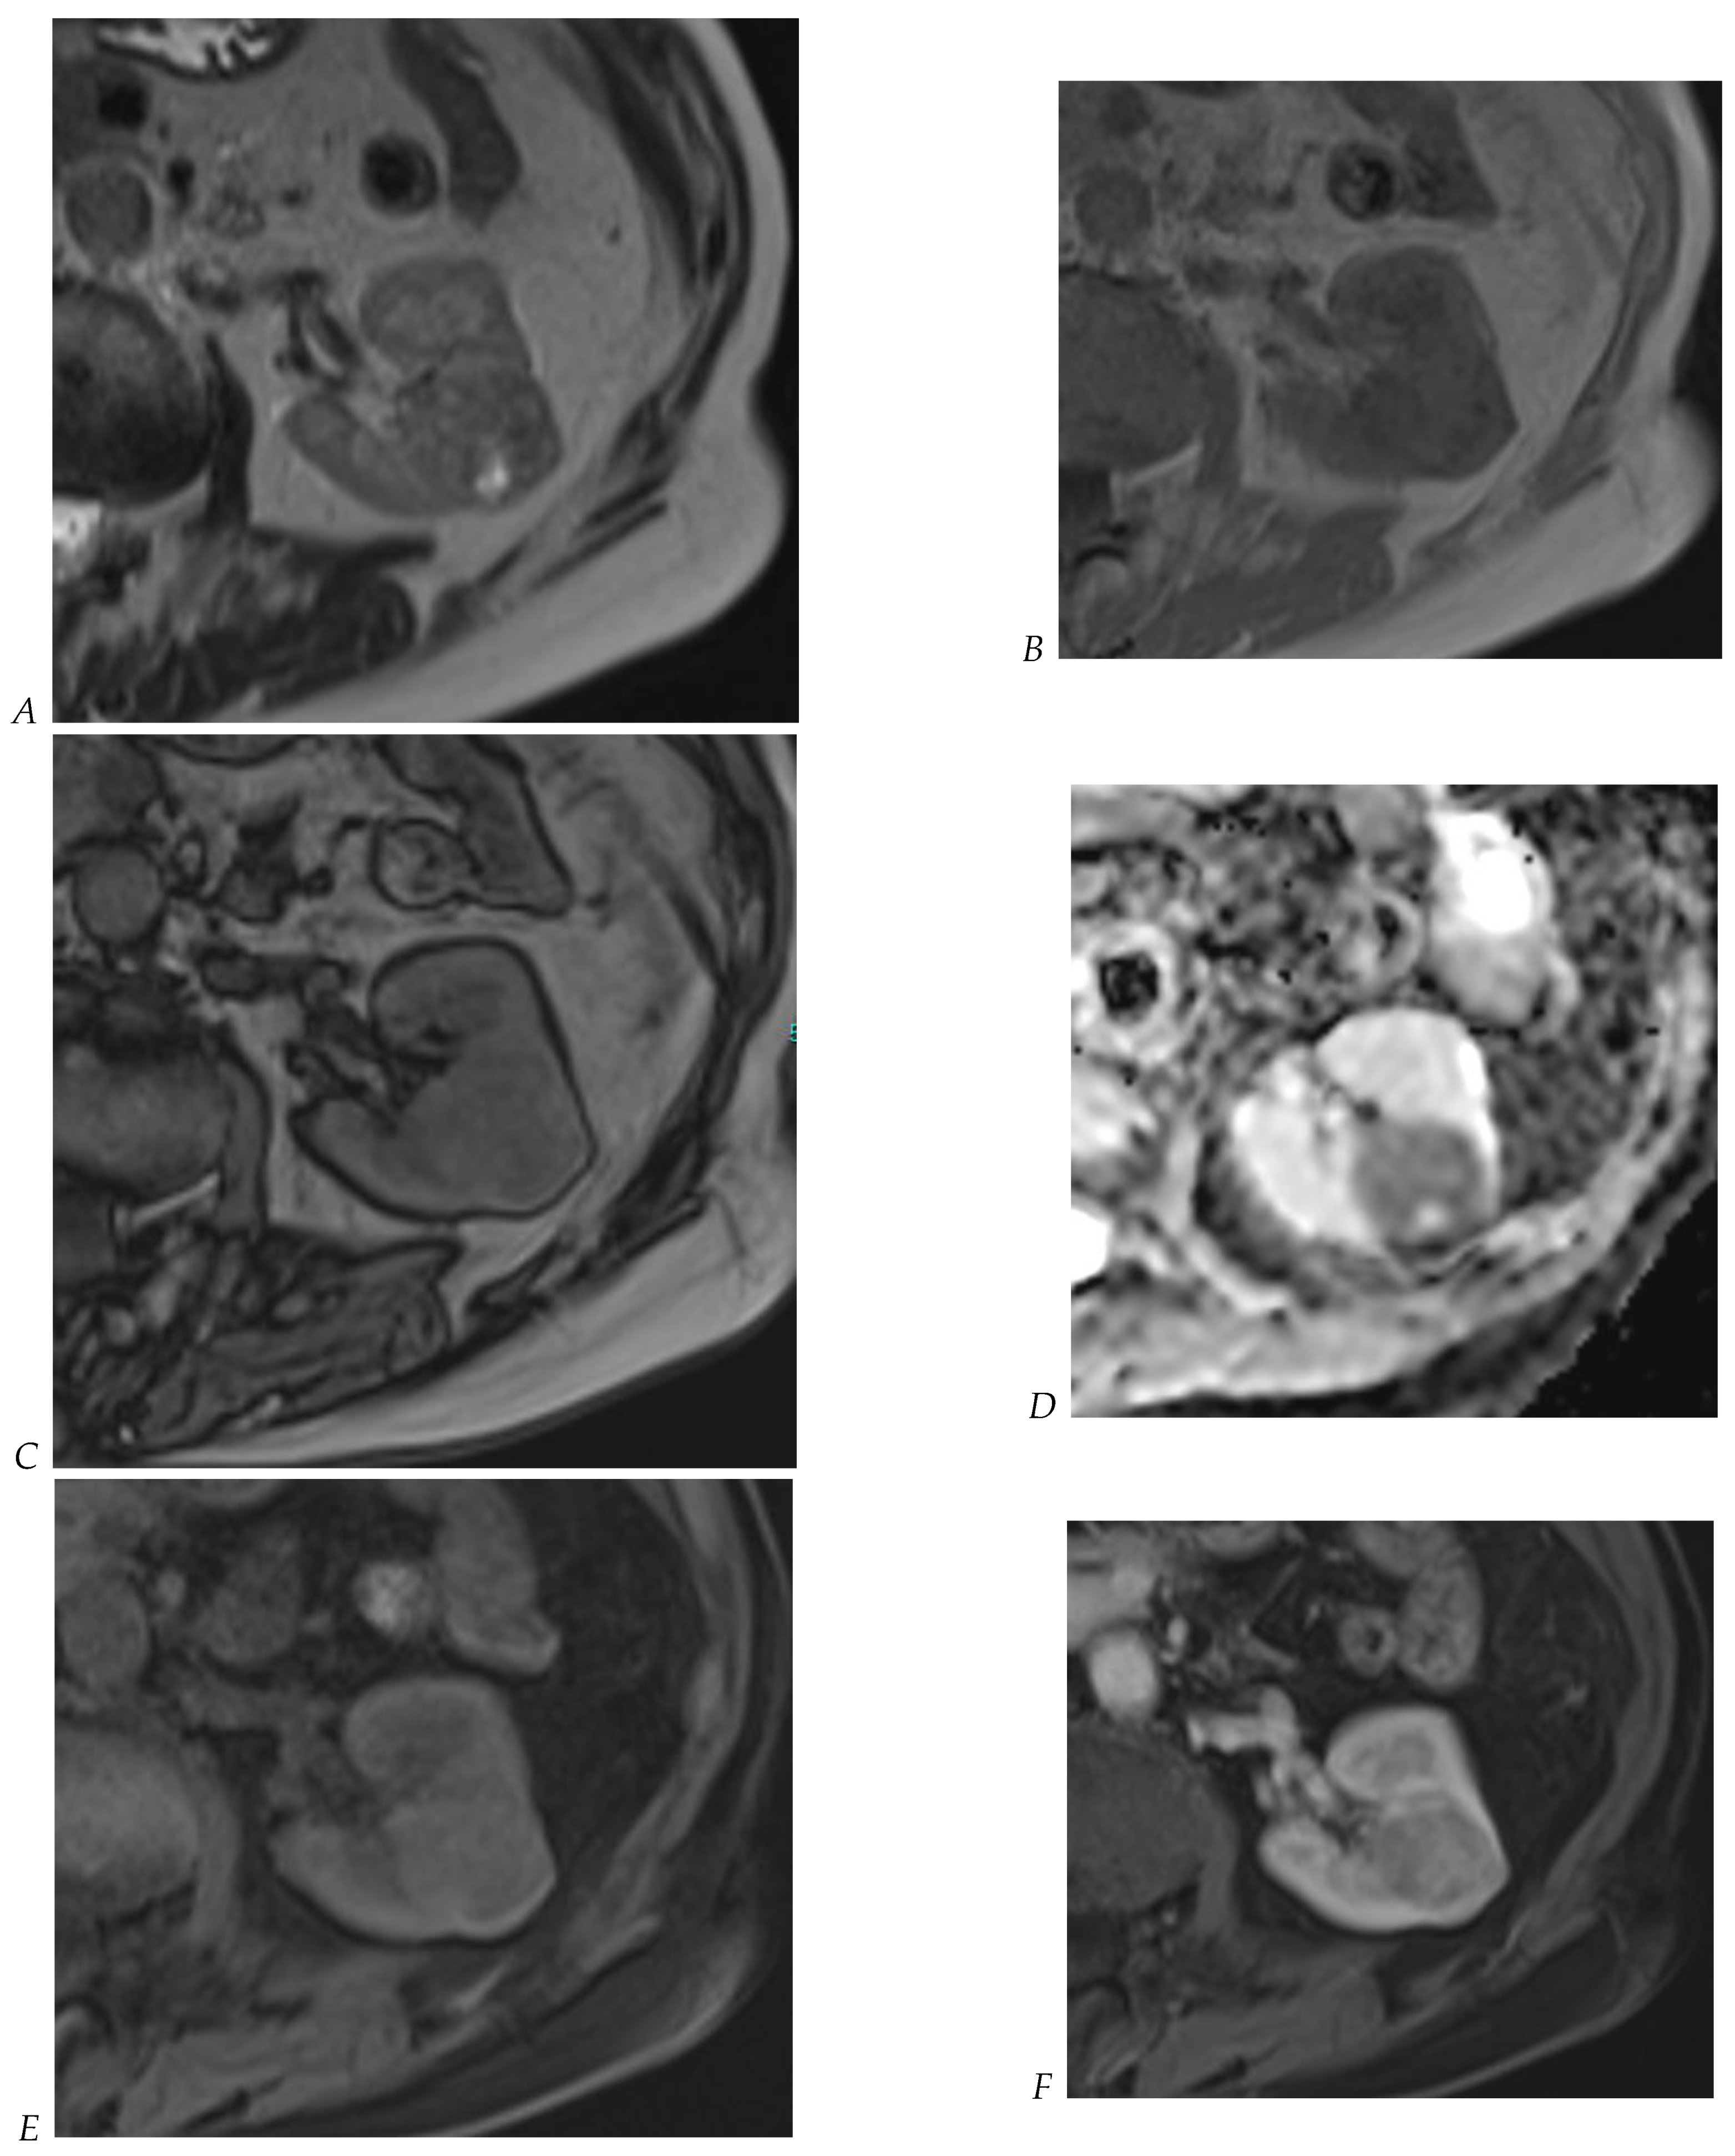

Figure 7.

Papillary renal cell carcinoma in the right kidney of a 75-year-old-woman. (A) Axial T2-weighted fast SE image shows a homogeneous 1.8 cm mass in the posterolateral region of the right kidney, with a lower SI compared to renal parenchyma. Transverse in-phase (B,C) opposed-phase MR images do not show a significant signal loss on the opposed-phase image. (D) The ADC map shows restriction of tumor diffusion into the renal mass. Transverse nonenhanced (E) and gadolinium-enhanced T1-weighted gradient-echo spoiled MR images in (F) corticomedullary, (G) nephrographic, (H) and delayed phase images show progressive enhancement without washout; the mass is hypovascular compared to the renal cortex.